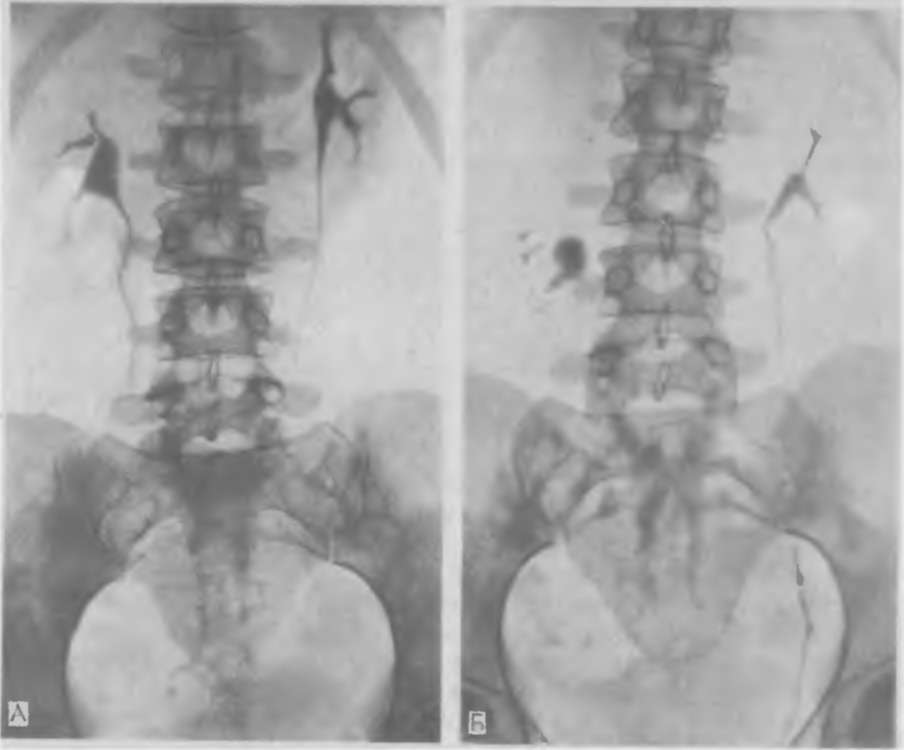

Экскреторная урография при нефроптозе: диагностические изображения